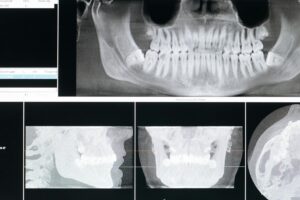

Sintomi della parodontite e possibili cure

La parodontite è un’infiammazione dei tessuti che sostengono il dente, chiamati complessivamente parodonto. Del parodonto fanno parte le gengive, il legamento parodontale e l’osso alveolare. Disturbo gengivale molto diffuso ma anche molto doloroso, tra i sintomi della parodontite c’è la possibile perdita dei denti in modo permanente. Per questa ragione, e data la delicatezza della […]

Parodontite: come rinforzare i denti che si muovono

Il nostro apparato masticatorio è composto da una struttura che contribuisce, tutta insieme, alla masticazione. L’intero apparato è controllato da un meccanismo neuromuscolare bilanciato. All’interno dell’apparato ci sono lingua, mandibola, muscoli facciali, mandibolari e mandibolari accessori, articolazioni, denti. I denti sono saldamente posizionati all’interno della gengiva grazie all’osso alveolare, ai legamenti e al cemento radicolare. […]

Parodontite: se trascurata può portare alla caduta dei denti

Una gengivite trascurata costituisce il terreno ideale per lo sviluppo di una parodontite, l’infiammazione acuta o cronica del parodonto. Sotto questo nome sono racchiusi gli elementi che tengono ancorato il dente alla sua sede, ovvero l’osso alveolare, la gengiva, il legamento alveolo-dentale e il cemento radicolare. L’infiammazione del parodonto, o più specificamente l’insieme delle malattie […]

Parodontopatia: come riconoscerla e come curarla

La parodontopatia è un’infiammazione acuta o cronica del parodonto, il complesso degli elementi che fissano il dente nella sua sede. In passato maggiormente conosciuta come piorrea, la parodontite è la causa più diffusa della perdita dei denti nell’adulto. Molto spesso sono le gengiviti a innescare il processo infiammatorio che porta poi a questa patologia, ma […]